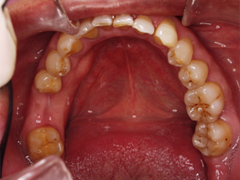

吉本歯科医院では、口内写真とパノラマレントゲンを撮影し、まずは顎の骨の状態まで詳しく確認しました。

写真(1)口内写真

正確な診断

院長の吉本の診断は以下でした

1.奥歯がない状態で過ごしていた期間が長いため歯がない部分に隣の歯が倒れだして全体の歯並びを崩しはじめている